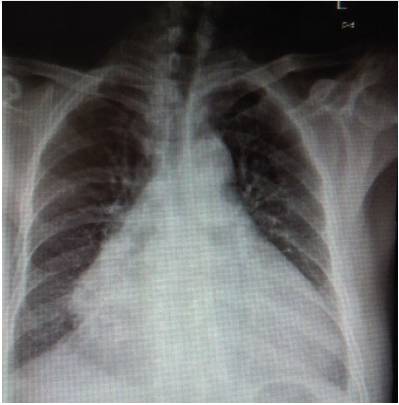

3、胸部正位片

●两肺纹理增多、紊乱。

●心影明显增大。